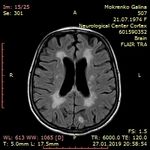

МРТ